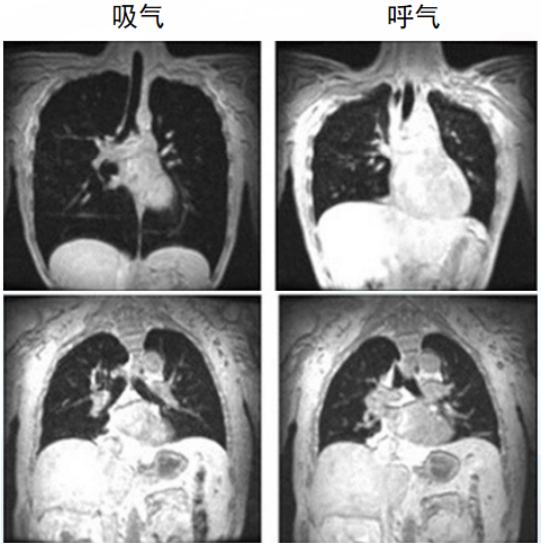

膈肌功能评估主要包括无创评估和有创评估。无创评估方法包括胸部影像学(胸部X线摄影、胸部CT、MRI)、肺功能、膈肌超声,有创评估方法包括压力测定(食道测压—跨膈压)、颤搐性跨膈压、膈肌肌电图。(1)胸部X线摄影:普通胸部X线摄影包括胸片与透视。胸片为静态检测手段,常用于单侧膈肌异常的诊断,如因肌纤维薄弱扩张所致的膈膨升、胸腹腔疾患所致的压力梯度异常或膈神经麻痹等。透视可动态评估膈肌的运动功能,是对胸片的进一步补充,并以观测膈肌运动幅度为主,但由于辐射及患者配合等问题在临床中并未广泛应用。图1为冠状动脉搭桥患者手术前后的胸片,术前胸片可见膈肌正常。术后2周患者出现呼吸困难,胸片可见左侧膈肌明显抬高,可能是由于术中损伤膈神经导致膈肌麻痹所致。(2)胸部CT:作为静态检测手段,胸部CT可以进行横断面扫描及三维重建,用于检测膈肌的器质性占位,三维重建能还原膈肌各部的立体结构,在残气量(RV)、功能残气量(FRC)、肺总量(TLC)等时相测量患者矢状位和冠状位的膈肌长度、表面积、膈穹隆、对合面积等,以此来量化膈肌的功能。图2所示为通过测量患者起病后第10天的膈肌宽度来估算膈肌的面积,结果发现膈肌面积缩小,提示存在膈肌萎缩及膈肌功能障碍。(3)胸部MRI/动态MRI:通过胸部MRI/动态MRI可以动态评估膈肌功能。如图3所示为正常人在TLC、FRC、RV三个体位时的膈肌形态,可以发现,从FRC到TLC时,膈肌明显下移。图4所示为对肌萎缩侧索硬化(ALS)患者膈肌进行的动态监测,在正常人在吸气和呼吸时,膈肌有明显的位移。但是ALS患者出现呼吸衰竭,无论是吸气还是呼气,膈肌位移都非常不明显,提示患者可能存在膈肌麻痹。

图3 正常人在TLC、FRC、RV三个体位时的膈肌形态